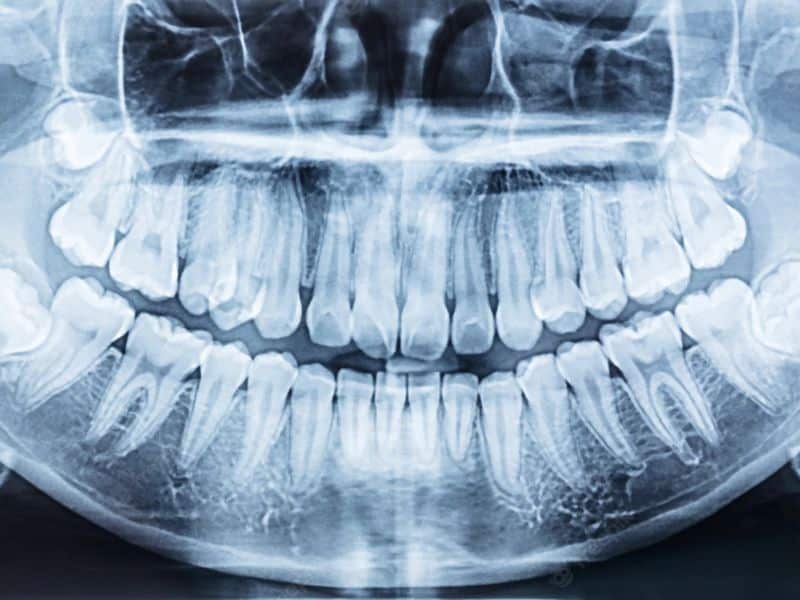

Panoramic X-ray

Digital dental X-ray diagnostics is an advanced technology that can create a complete, two-dimensional overview of all your teeth within minutes. A panoramic X-ray provides the dentist with a comprehensive picture of the condition of the teeth, jawbone, and surrounding structures, enabling an accurate diagnosis and an effective treatment plan.

A panoramic X-ray is a dental imaging procedure that shows the entire dentition, jaws, and surrounding anatomical structures in a single image.

It provides the dentist with a comprehensive view of the oral cavity, allowing not only visible problems but also hidden changes to be detected in time.

Orthopantomography, or digital X-ray diagnostics, is an advanced technology that can create a complete, two-dimensional overview of all your teeth, the upper and lower jaws, both temporomandibular joints, and the nasal and sinus cavities within minutes.

It can also identify changes due to accidents or diseases, clearly showing cysts, tumors, fractures, impacted teeth, as well as inflammatory conditions and the extent of gum recession. Digital machines produce very high-quality, clear images.